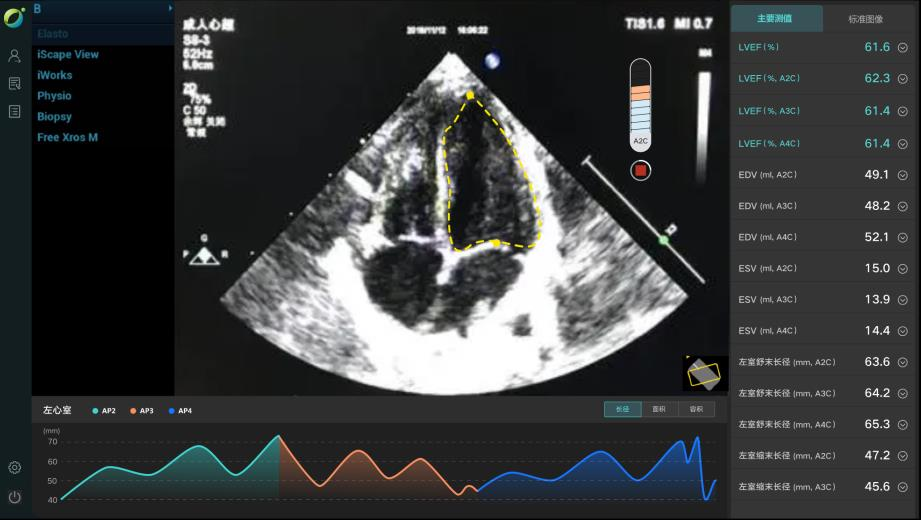

除上述肺結(jié)節(jié)人工智能篩查示例外,目前已形成了全鏈路人工智能產(chǎn)品解決方案,在影像、超聲、病理方面都與AI智能影像輔助診斷技術(shù)高效結(jié)合,幫助醫(yī)院實(shí)現(xiàn)自動(dòng)化、高精度的影像診斷檢查,讓患者在疾病篩查中實(shí)現(xiàn)早期診斷、預(yù)測(cè)、治療、療效評(píng)估與監(jiān)測(cè)。